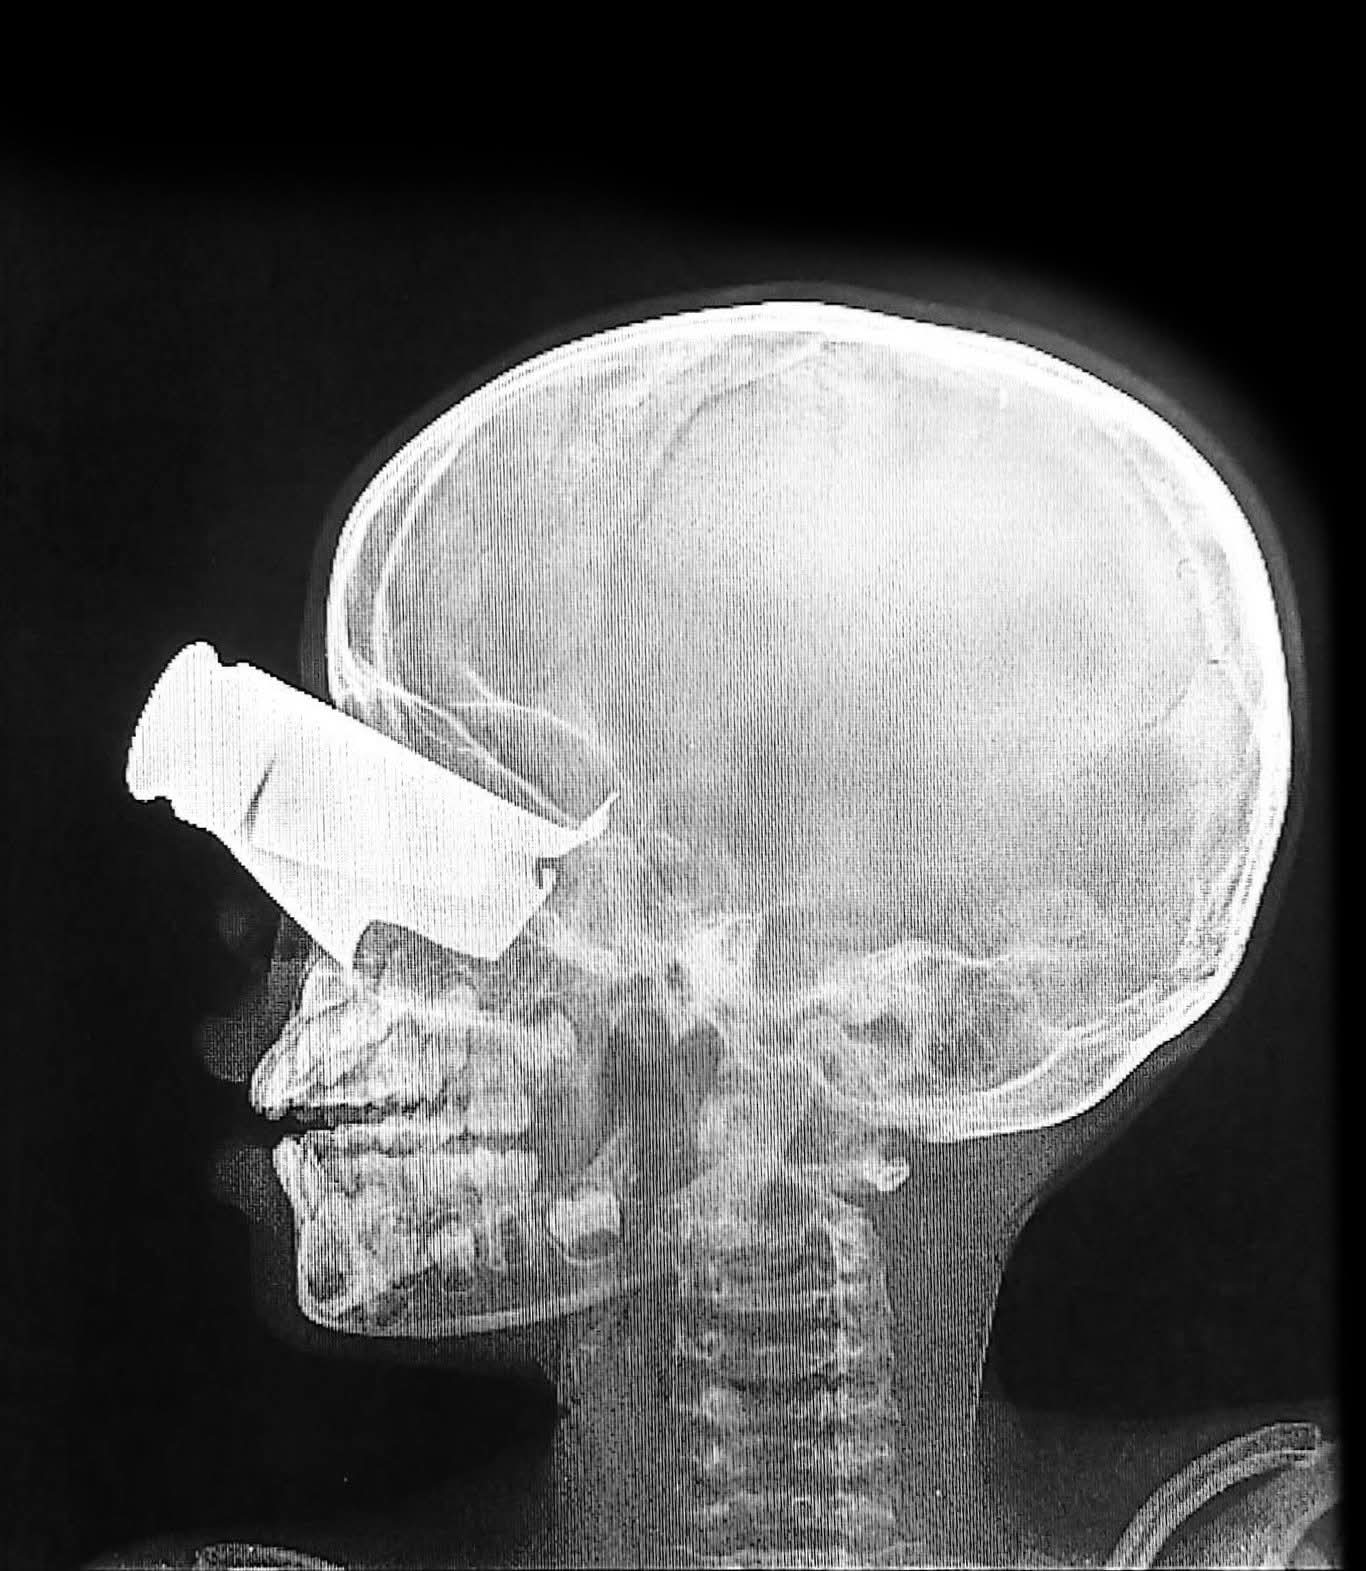

TINE, 6 février – Un garçon de 9 ans a été grièvement blessé à la tête par un shrapnel lors d’une attaque de drone dans l’ouest du #Soudan. La radiographie, réalisée à l’hôpital de Tiné dans l’est du #Tchad, illustre la gravité de ses blessures. « Même avec des soins optimaux, il risque de souffrir d’une invalidité à long terme », avertit Virginia Moneti, coordinatrice médicale de MSF.

Au cours des deux premières semaines de février, les équipes médicales de MSF ont traité 167 patients victimes de blessures pénétrantes au thorax ou à l’abdomen, de fractures multiples, de traumatismes crâniens et d’éclats d’obus causés par les drones.